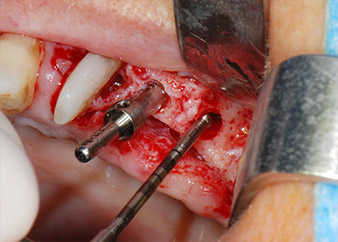

Un mese più tardi, nel giorno programmato per l'intervento, il dolore e l'infiammazione in corrispondenza del dente 24 erano minimi, ma era ancora presente mobilità di classe 2 secondo Miller. Dopo l'apertura dei lembi e la pulizia del tessuto periapicale e periradicolare infetto, l'estensione della mancanza ossea si è resa evidente (Figg. 2 e 3).

Tutto il tessuto osseo vestibolare e distale era mancante in corrispondenza della radice buccale. La possibilità di attacco era essenzialmente ristretta alla radice palatale, evidenziando la prognosi negativa preliminare. Anche il dente 27 mostrava un punto di attacco orizzontale ridotto e una rarefazione apicale minima (cfr. Fig. 1), senza sintomi clinici.

Si è mantenuta , tuttavia, l'idea iniziale di conservare entrambi i denti come appoggi temporanei del ponte durante il periodo di sei mesi per l'osteointegrazione degli impianti. In seguito la situazione si sarebbe assestata. In primo luogo, in un tentativo di risolvere il problema entro-periodontale, la superficie radicolare rimanente è stata attentamente sbrigliata con apparecchiatura piezoelettrica (Piezomed di W&H con l'attacco S1 a spatola, progettato in origine per l'erosione della parete laterale del seno mascellare) Fig. 4).